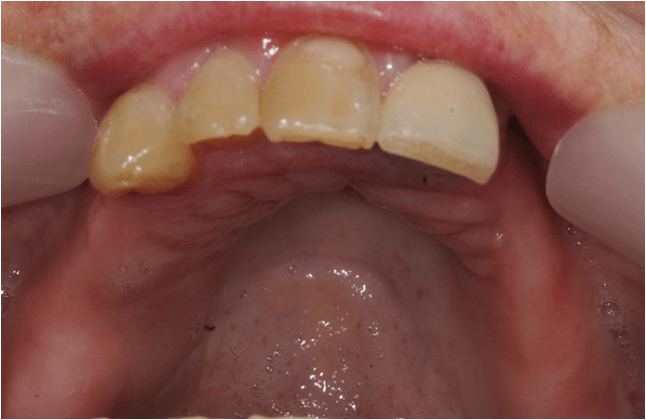

Direct composite is often used to treat toothwear. It is a minimally invasive method that does not damage the underlying tooth structure. It can chip, stain and fail. However, replacement and repair is more straightforward. This case was treated with direct composite alone.

Another case of mild toothwear and discolouration was treated with direct composite bonding.